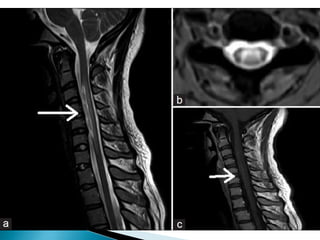

 Radiological characteristics include a central longitudinal

and extensive cervicodorsal lesion (three or more spinal

segments) with spinal expansion, of low signal in T1

sequences and high signal in T2 sequences and patchy

enhancement.

 It has been demonstrated that 60% of patients may have

periventricular lesions (areas of high aquaporin 4

concentration).

 In this case, NMO is not associated with cerebral white

matter lesions, and the spinal lesions are confluent and

extend to multiple segments (which is infrequent in MS);